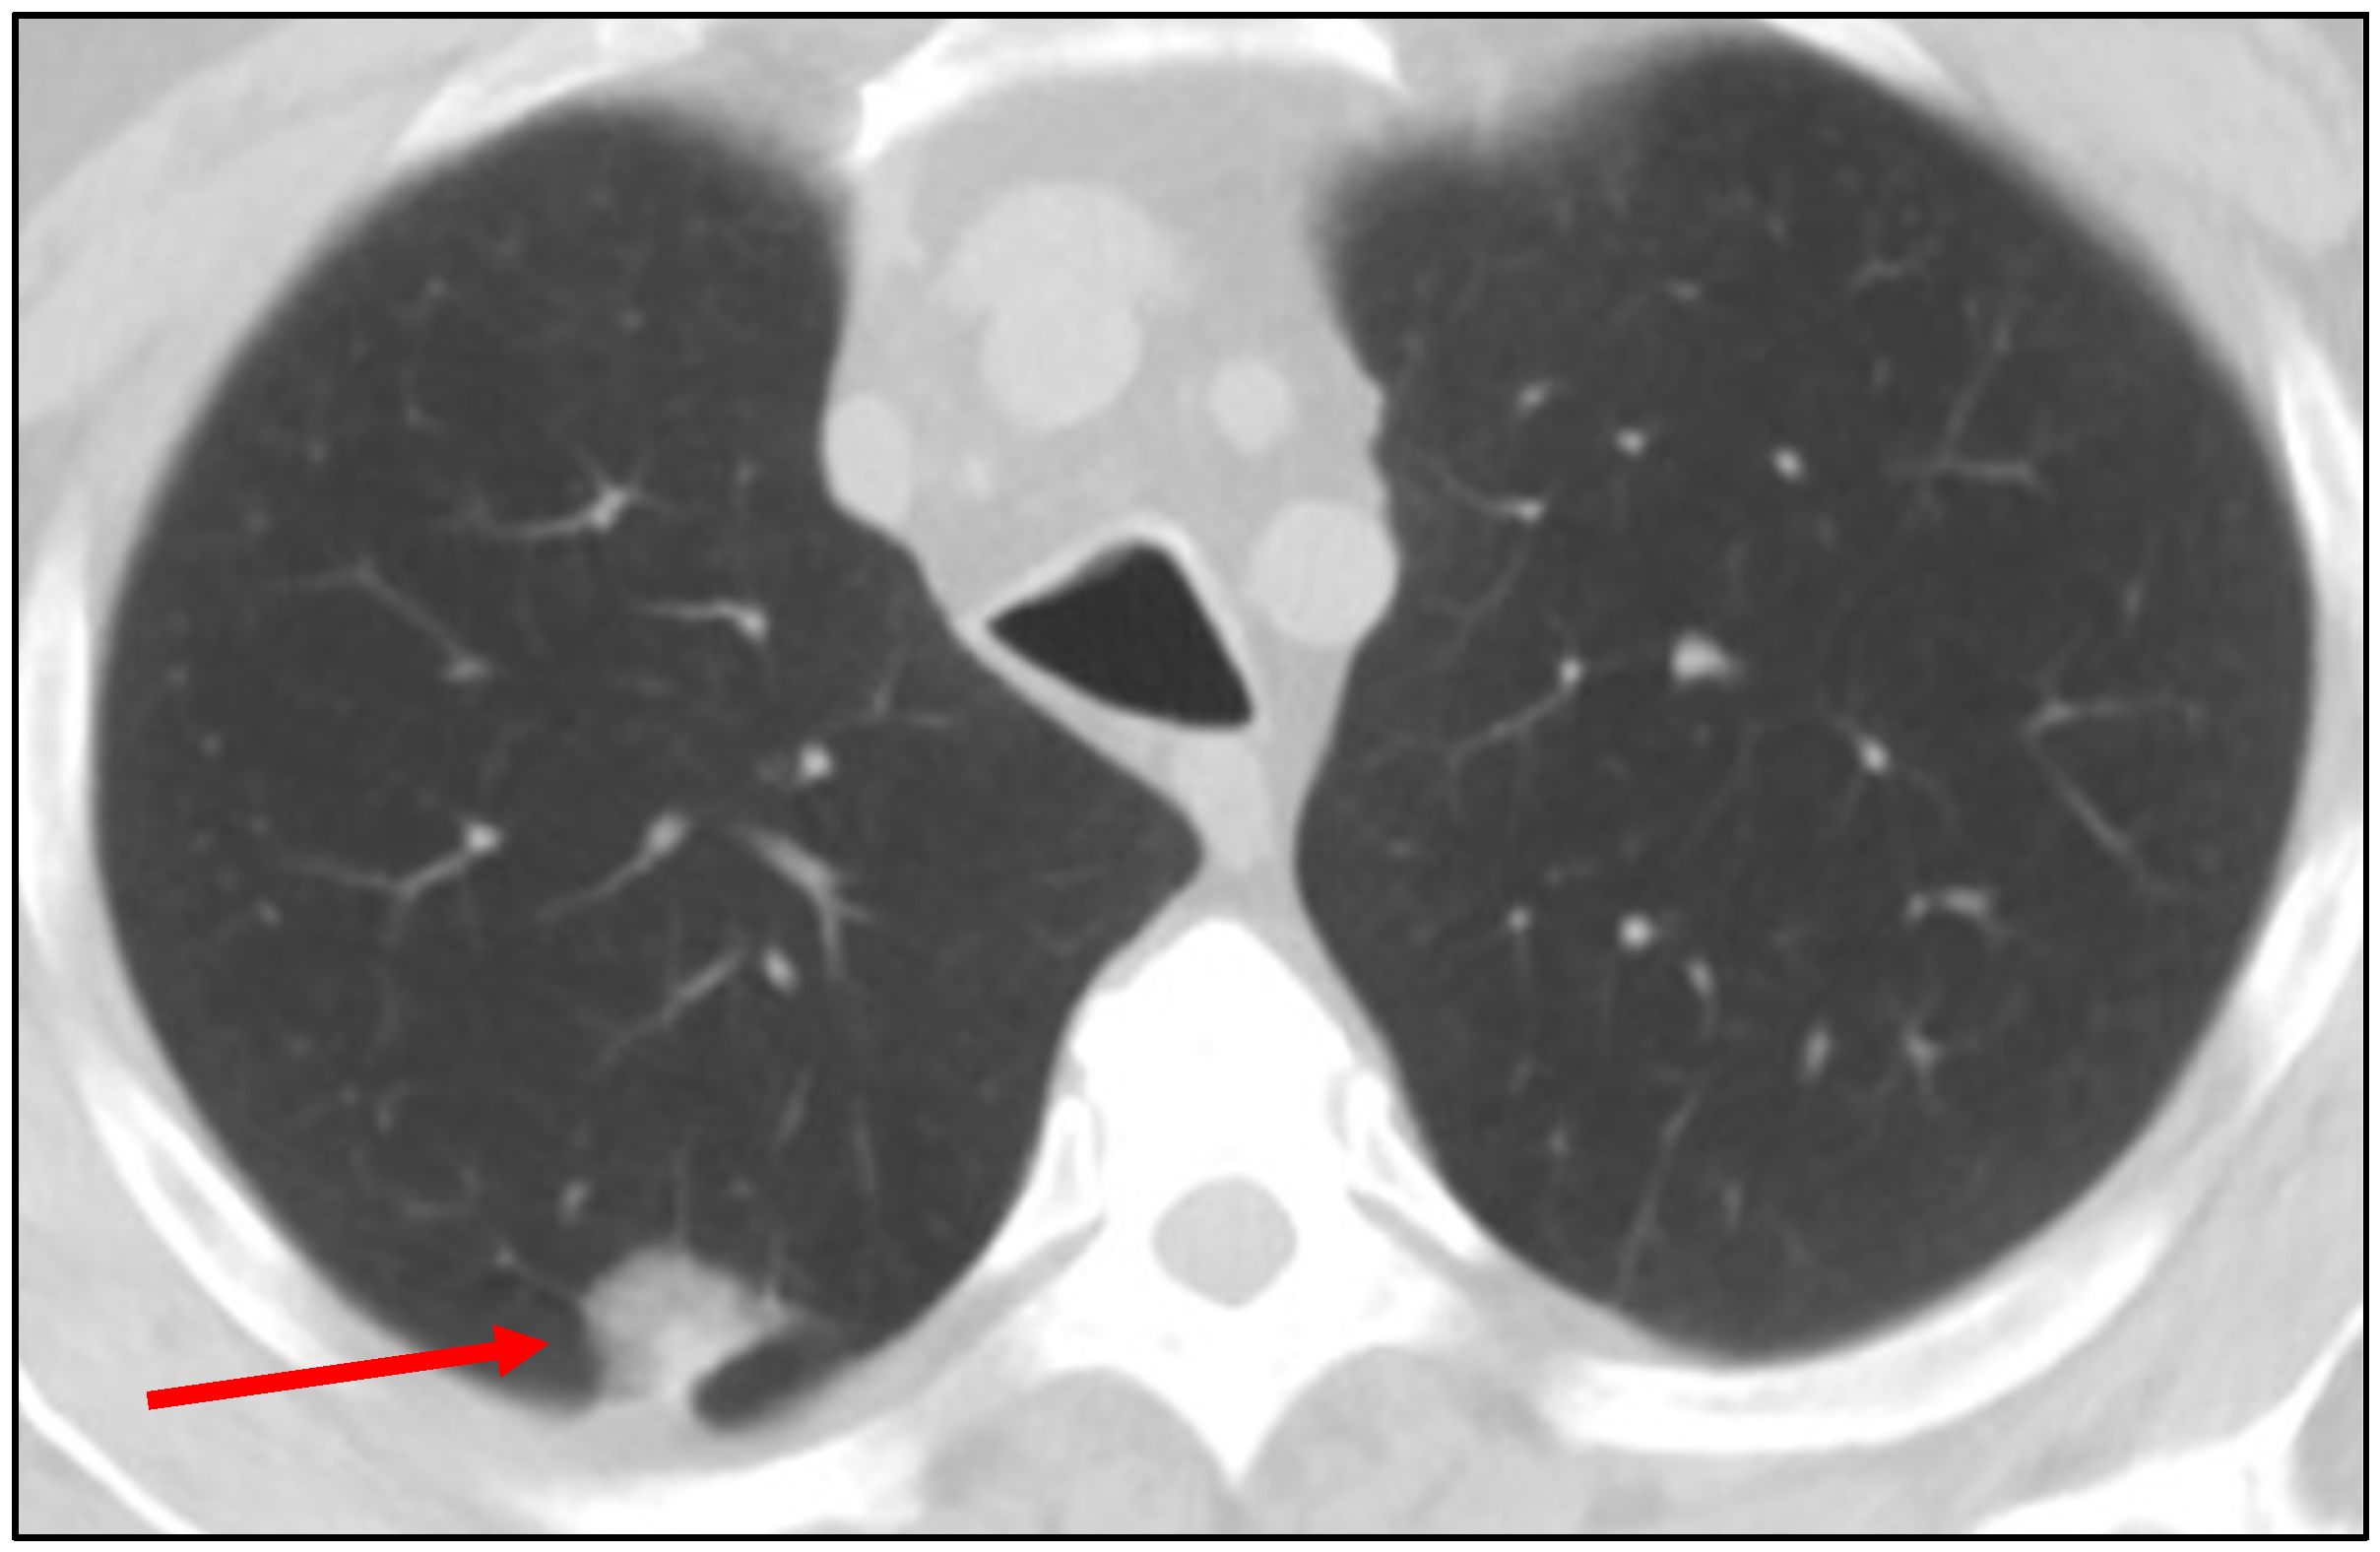

2. Clinical Challenge: A Representative Case